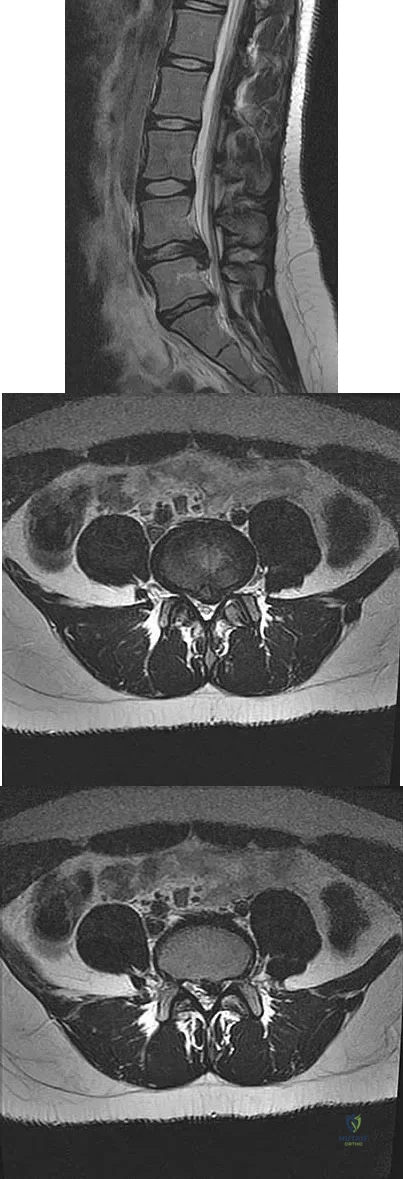

A 50-year-old man with no history of trauma reports new-onset back pain after doing some yard work the previous day. He reports pain radiating down his leg posteriorly and into the first dorsal web space of his foot. MRI scans are shown in Figures 3a through 3c. What nerve root is affected?

Explanation